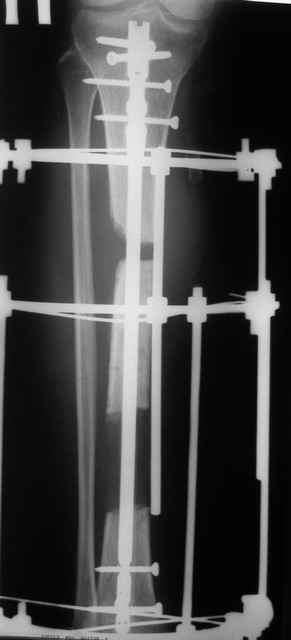

Тогда можно рассмотреть вопрос одновременного удаления штифта, мышечной (в данной области применим проксимально отсеченный лоскут камбаловидной мышцы) или микрохирургической (что более надежно) пластики дефекта мягких тканей, остеотомии проксимального фрагмента большеберцовой кости, остеосинтеза блокируемым штифтом с а/б покрытием, наложения простого аппарата Илизарова (можно из полуколец) для дистракции на штифте. При данном варианте пациент сохраняет возможность полной опоры на ногу, что очень важно для заживления у пожилого пациента) и отпадает необходимость в проведении дополнительный операций (при благоприятном развитии событий).

Выкладываю картинки похожей пациентки. Извините, что без окончательных снимков (сейчас их нет под рукой). Правда мы имели проблемы у данной больной после снятия аппарата, когда промежуточный фрагмент большеберцовой кости сместился на 1,5 см дистально и отошел от проксимальной части кости. До сих пор у пациентки на снимках определяется лишь тонкая полоска кости по задней поверхности за штифтом (образовалось что-то вроде маленького регенерата)в области стыковки промежуточного и проксимального фрагментов. Больная пока решила подождать. Не хочет оперироваться, так как ходит не хромая, работает.

Кратко: мужчина за 60 лет получил травму 28 лет назад (переехало автобусом). Оперировался десятки раз, в итоге с очередным патологическим переломом, хронической язвой и гипсовой лонгетой попал ко мне... Объективно - остеомиелит, инфицированный ложный сустав (или как его назвать), флегмона по наружной поверхности

голени, укорочение около 5 см.

На операции резекция 8 см, внешний остеосинтез,одновременное сближение примерно на 4 см, а затем постепенное сближение до полного контакта в течение 3 недель. Рана с патологически измененными краями, имевшая на операции размеры примерно 4-5 на 10-12 см закрылась самостоятельно в течение примерно 2-х мес. Ну не самостоятельно, конечно, а с нашей помощью, но без пластики.

Сейчас в аппарате вытянул около 6 см в верхней трети.